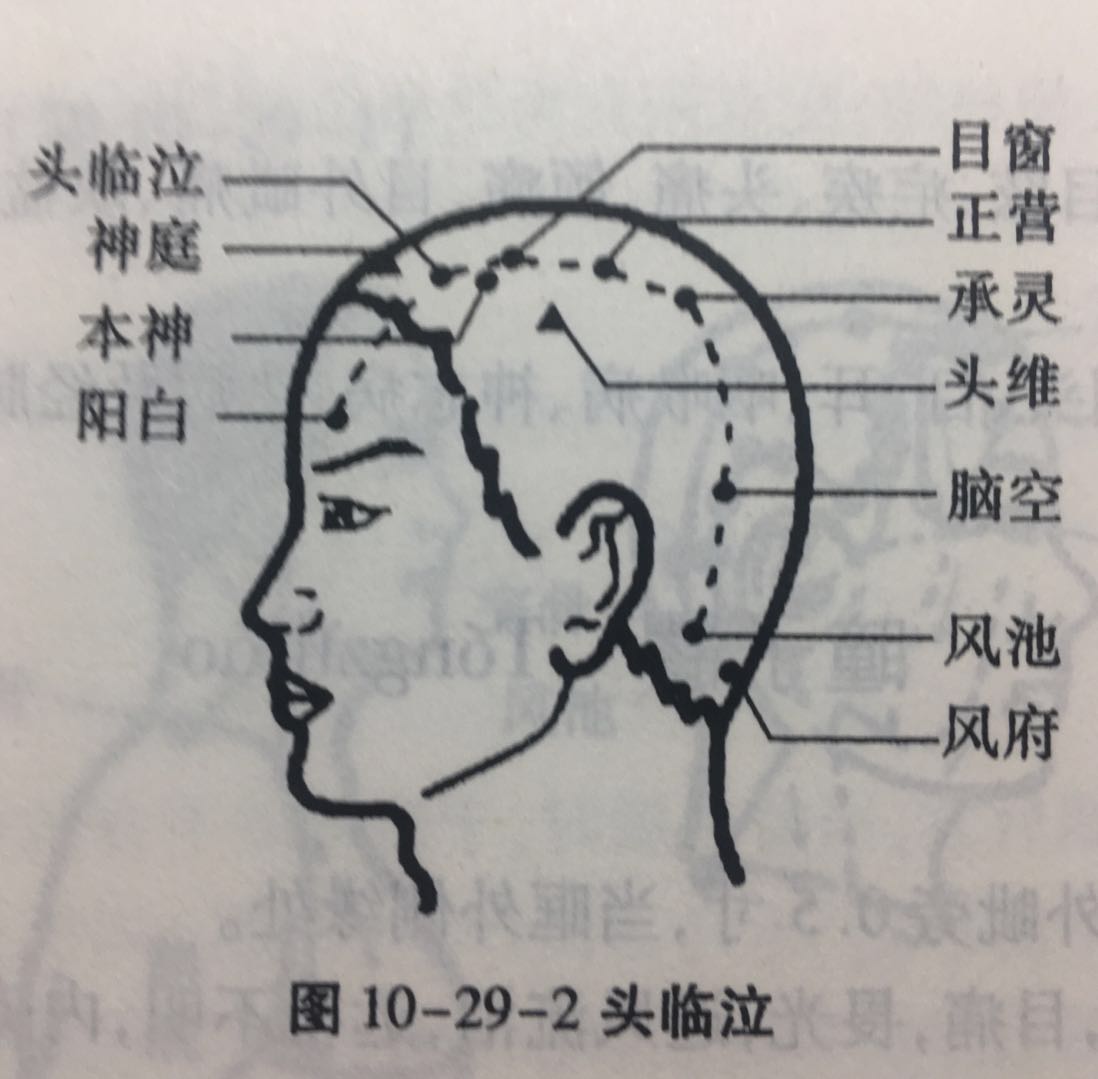

头临泣

【定位】 在头部,当瞳孔直上入前发际 0.5 寸,神庭与头维连线的中点处(图 10-29-2)。

【主治】 头痛,目眩,目赤痛,流泪,目翳,鼻塞,鼻渊,耳聋,小儿惊痫,热病。

【配伍】 配阳谷、腕骨、申脉治风眩,配肝俞治白翳,配大椎、腰奇、水沟、十宣治中风昏迷,癫痫,配大椎、间使、胆俞、肝俞治疟疾。

【刺灸法】 平刺 0.5 ~ 0.8 寸;可灸。

【附注】 足太阳、少阳、阳维之会。